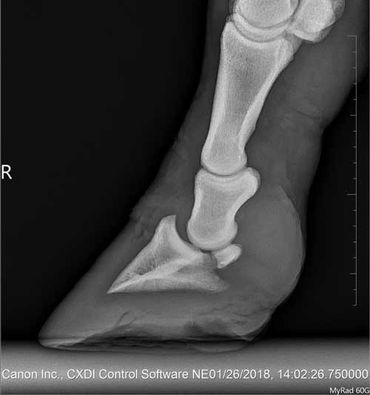

We had the vet back out again on August 3, 2020 because Zoe didn´t do well long after her injections. She got really lame again and she had the hardest time walking.

The vet did one more injection into the pastern joint, but he went in from the back of the leg and this time all the fluid went into the joint.

In addition we had a intrasynovial-centesis to the flexor tendon done.

The cost for the treatment was $615 which also included the lameness exam, some more radiographs, sedation and the farm call.